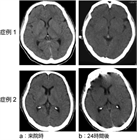

1. 低(無)酸素・虚血後脳症とは、脳の灌流低下や低酸素血症によって起こる脳の全体的な障害状態である。

1. 診断は、病歴にて行う。心停止や気道異物による窒息、入浴中の溺水などにより、バイタルサインが回復しても意識障害が持続する場合は、低(無)酸素・虚血後脳症を疑い原因の評価と加療の検討を始める(推奨度1)

1. 全身性の病態に引き続いて発生することが多く、特に心筋梗塞、致死性不整脈や重症肺炎、急性呼吸窮迫症候群や肺塞栓などの心肺疾患や急性中毒が重要である。臨床的には、極端な低血圧(収縮期血圧<60mmHg)、心停止や気道異物による窒息が原因となることが多い。